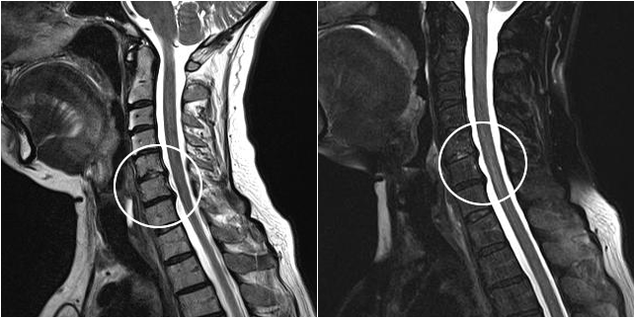

Modern teşhis yöntemleri, kıkırdak ve kemik dokusunun tahribat süreçlerini en doğru şekilde incelemeyi mümkün kılan MRI ve BT'yi içerir. Ayrıca bu tekniği kullanarak hastalığın kaynağına yakın fıtıklar ve diğer yumuşak doku defektlerini teşhis etmek de uygundur.